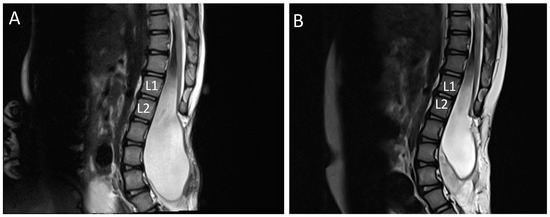

- KUB ultrasound has to be performed one month before and after the untethering surgery. Follow-up appointments are between three and six months depending on urological management